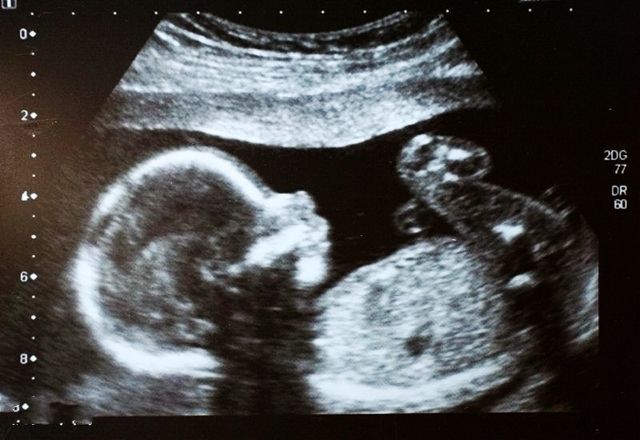

听到“脐带绕颈”这四个字,多数人脑海里浮现出的是胎儿脖子被脐带紧绕,甚至无法呼吸的恐怖画面。这也导致很多孕妇在产检的时候,听到医生说胎儿脐带绕颈就紧张到不行。但事实上,脐带绕颈真的有那么可怕吗?孕妇心里要有数,可别吓自己。

脐带是连接胎儿和孕妇的桥梁,在整个孕期,脐带都有着重要的作用。脐带的一端连着胎儿的腹壁,也就是之后的肚脐;另一端连着胎盘。脐带是胎儿和母体进行物质交换的重要通道,正常的脐带都是附着在胎盘的中心。一般情况下,在怀孕12周左右,通过超声就能看到脐带的影像了。

脐带的长度基本上和胎儿的长度是一致的,足月胎儿的脐带长度在30-70厘米之间。而胎儿除了睡觉之外,也会做各种活动,尤其是会将脐带当做玩具来玩耍。那在这个过程中,脐带就可能会缠绕在胎儿的脖子上、脚上、身上等。

脐带绕颈是孕期常见的现象,发生率在30%左右。大部分的脐带绕颈都是很松的,胎儿和脐带都是在羊水中,只是脐带在颈部漂浮着而已。而且大多数的脐带绕颈只有一两周,胎儿在之后的活动中也会绕出来的,并不会影响到胎儿的健康,所以孕妇不用太过担心。不过,如果脐带绕颈圈数较多,或者是绕的比较紧的话,那就要引起注意了。